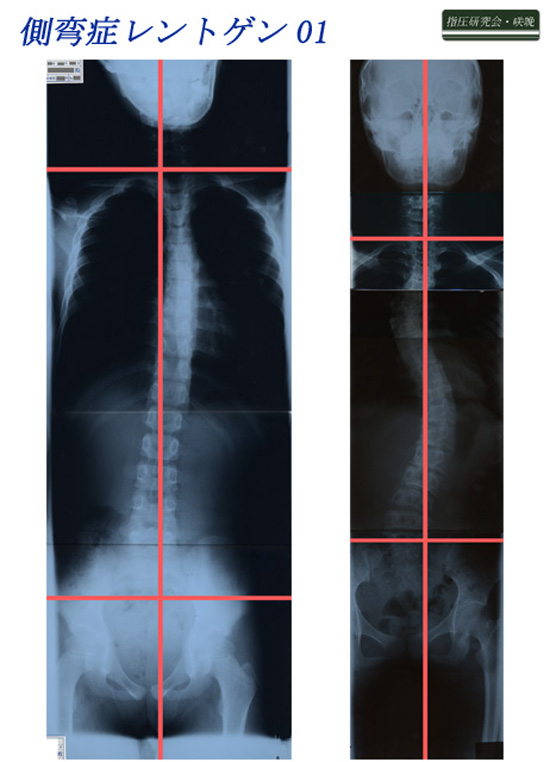

脊柱側弯症レントゲン01

脊柱側弯症レントゲン2例を紹介します。

臨床において脊柱側弯症に性差を感じます。私が典型的な性差と感じる症例を紹介しました。

臨床効果を上げるために脊柱側弯症の性差は重要だと体験を通じて感じています。